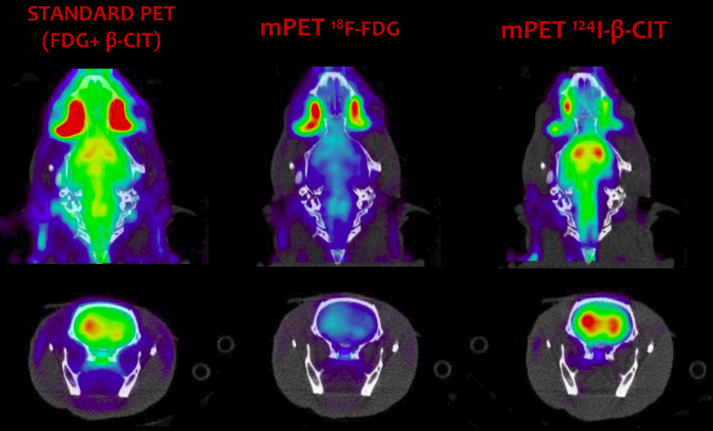

| ABSTRACT | Introduction: Simultaneous in-vivo imaging of several biological processes may improve oncological, neurological and cardiovascular studies by providing complementary information obtained under the same exact conditions and coregistered in space and time. Standard PET imaging does not allow multiplexed acquisitions, as all annihilation photons have the same energy. We developed a technique called multiplexed PET (mPET), which uses a tracer labelled with a pure positron emitter (such as 18 F, 13 N, 11 C), and a tracer labeled with a positrongamma emitter (such as 124 I, 76 Br, 82 Rb, 86 Y). Positrongamma emitters generate a significant number of triplecoincidences , which allows them to be differentiated from the standard PET radionuclides . In this work, we evaluated the performance of mPET using phantom and animal experiments. |

| JOURNAL | IEEE Nuclear Science Symposium & Medical Imaging Conference, 2014 |

| ABSTRACT | Positron emission tomography (PET) is one of the most sensitive noninvasive molecular imaging tool, being its sensitivity several orders of magnitude higher than that typically obtained in single photon emission computed tomography (SPECT). However, PET lacks the ability of SPECT to multiplex signals from several tracers, which is very useful in many different studies such as cardiac imaging with 99mTcSestamibi and 201Tl. Recently, it has been shown that the use of tracers labelled with positrongamma emitter radionuclides like (124I, 86Y, 82Rb, 94mTc, 76Br) in combination with tracers labelled with standard positronemitter radionuclides like (18F, 11C, 13N) enables multiplexed PET (mPET). mPET uses the triple coincidences from the positrongamma emitters, together with the standard double coincidences to reconstruct separated images of each radionuclide’s activity distribution. We obtained encouraging results with mPET in some initial preclinical studies, but a detailed study of the quality and quantification properties of mPET images, and an evaluation of its performance in realistic clinical scenarios was still required. |

| ABSTRACT | Simultaneous invivo imaging of the biodistribution of two or more radiotracers of interest with Positron Emission Tomography (PET) could provide more comprehensive information about specific targets and physiological processes of interest; however, conventional PET cannot separate different positronemitting radionuclides based on the energy of the detected gamma photons. We have shown previously that the detection of triplecoincidence events allows the separation of radiotracers labeled with positron + gamma emitters (like 124 I) from others labeled with standard pure positron emitters (like 18 F), without requiring any kinetic modelling or precise energy measurement. The goal of the current study was to demonstrate that this methodology can also be applied to clinical PET scanners. |